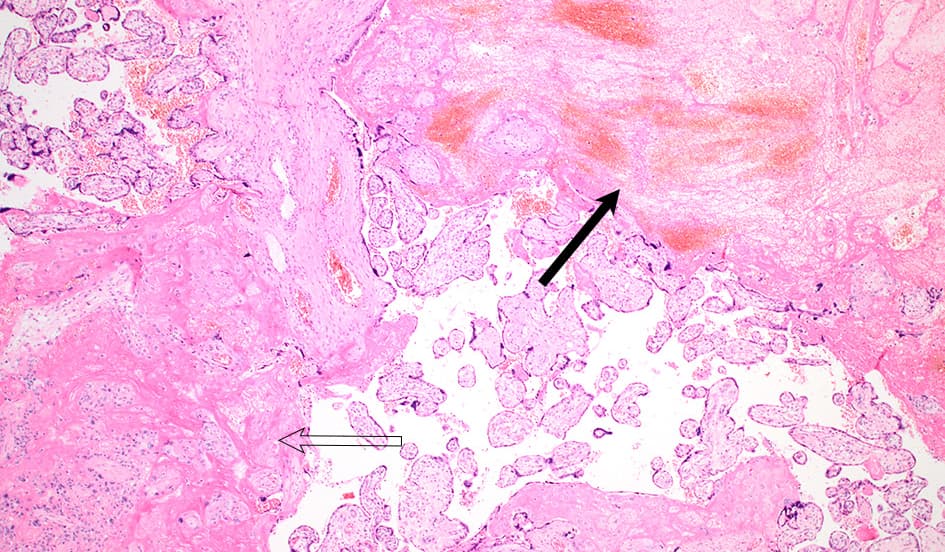

Histologisk undersøgelse af placenta (Figur 1) viste konfluerende organiserede intraplacentære hæmatomer, rigelige fibrinaflejringer, infarcerede villi chorii og organiserede intervilløse tromber af intermediær og ældre dato. Der var hverken akut eller kronisk intervillositis. Ved immunhistokemisk undersøgelse (IHC) kunne man ikke påvise SARS-CoV-2-nukleokapsid.